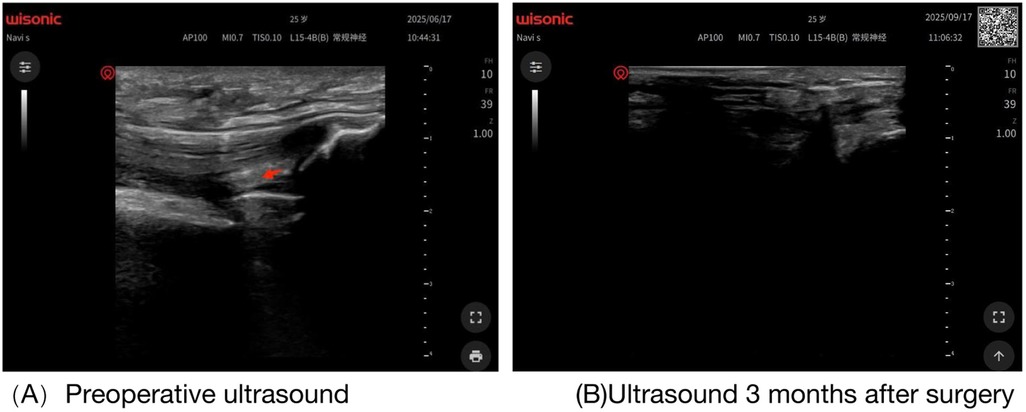

Patients with end-stage hemophilia often require total knee arthroplasty (TKA); however, the incidence of postoperative joint adhesions in these patients is significantly higher than that in the general population. Furthermore, due to their impaired coagulation function, the bleeding risk associated with traditional open adhesiolysis is also higher in this patient cohort than in the general population, and conservative rehabilitation therapy yields suboptimal outcomes. Thus, there is an urgent clinical need for a safe and effective intervention regimen. This study reports a 25-year-old male patient with severe hemophilia A (factor Ⅷdeficiency), whose baseline factor Ⅷactivity was 0.8%. Severe knee joint adhesions occurred 3 months after TKA, manifested as difficulty in walking, sitting, and standing. A combined treatment regimen of "perioperative precise coagulation factor replacement + ultrasound-guided acupotomy release under anesthesia + graded manual release" was adopted for the intervention of post-TKA adhesions in patients with severe hemophilia A. The results showed that this combined regimen may represent a feasible minimally invasive option for the clinical management of post-TKA adhesions in severe hemophilia A patients.